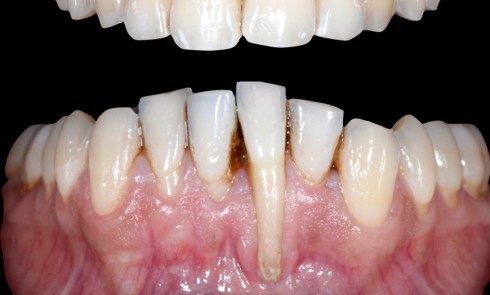

Article réservé à nos abonnés La chirurgie muco-gingivale du dépistage aux soins postopératoires

Les récessions gingivales Les récessions gingivales sont définies comme « le déplacement de la gencive marginale apicalement à la jonction amélo-cémentaire »...